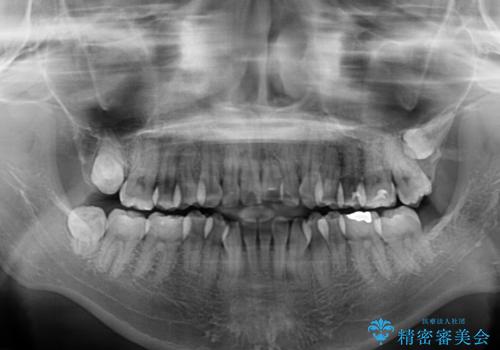

- 上下前歯の隙間と、外側を向いていて歯磨きのしにくい奥歯を気にして来院された患者様です。

下顎前歯が1本欠損しており、上下アーチはアンバランスとなりますが、インビザラインを用いて上下の隙間を改善しながら歯列を整えることとしました。

外側を向いている奥歯は、内側にアンカースクリューを埋入して牽引の固定ゲント氏、部分的にワイヤー装置を用いることで歯列に納めることとしました。

下顎前歯の1本欠損により左右の咬合が不安定となり、治療経過で噛みにくい状態が続きましたが、最終的には違和感なく噛めるようになりました。